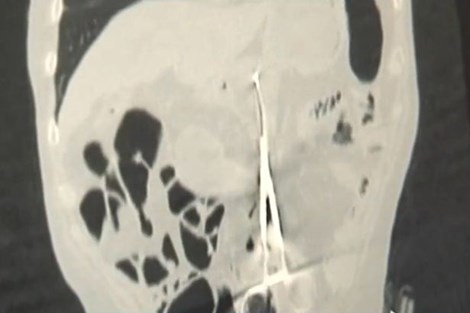

(PLO) - Các bác sĩ vụng về đã khiến một người đàn ông bị đau dạ dày suốt 12 năm vì họ đã vô tình bỏ lại một cái kéo.

Karp Ponomaryov (53 tuổi, Kazakhstan) đã trải qua một cuộc phẫu thuật để cứu mạng sống 12 năm trước. Nhưng các bác sĩ vụng về đã bỏ quên 1 cái kéo phẫu thuật dài 20 cm trong bụng ông.

Từ đó, Karp phải chịu đựng những cơn đau dạ dày dữ dội sau mỗi lần ăn no. Nhưng ông không bao giờ than phiền vì ông nghĩ rằng mình còn sống sót sau cuộc phẫu thuật là đã hạnh phúc rồi.

Tuy nhiên, một tháng trước, ông bắt đầu cảm thấy ăn không ngon miệng và sụt cân. Karp đã phải đi khám bệnh. Bác sĩ chụp X-quang Baurzhan Aybaev cho biết: “Tôi chưa bao giờ thấy bất cứ thứ gì như thế này. Thỉnh thoảng cũng có bác sĩ để quên bông gạc trong người bệnh nhân, nhưng một dụng y tế lớn như vậy thì nên tránh sai lầm hoặc ít nhất cũng nên phát hiện sớm hơn”.